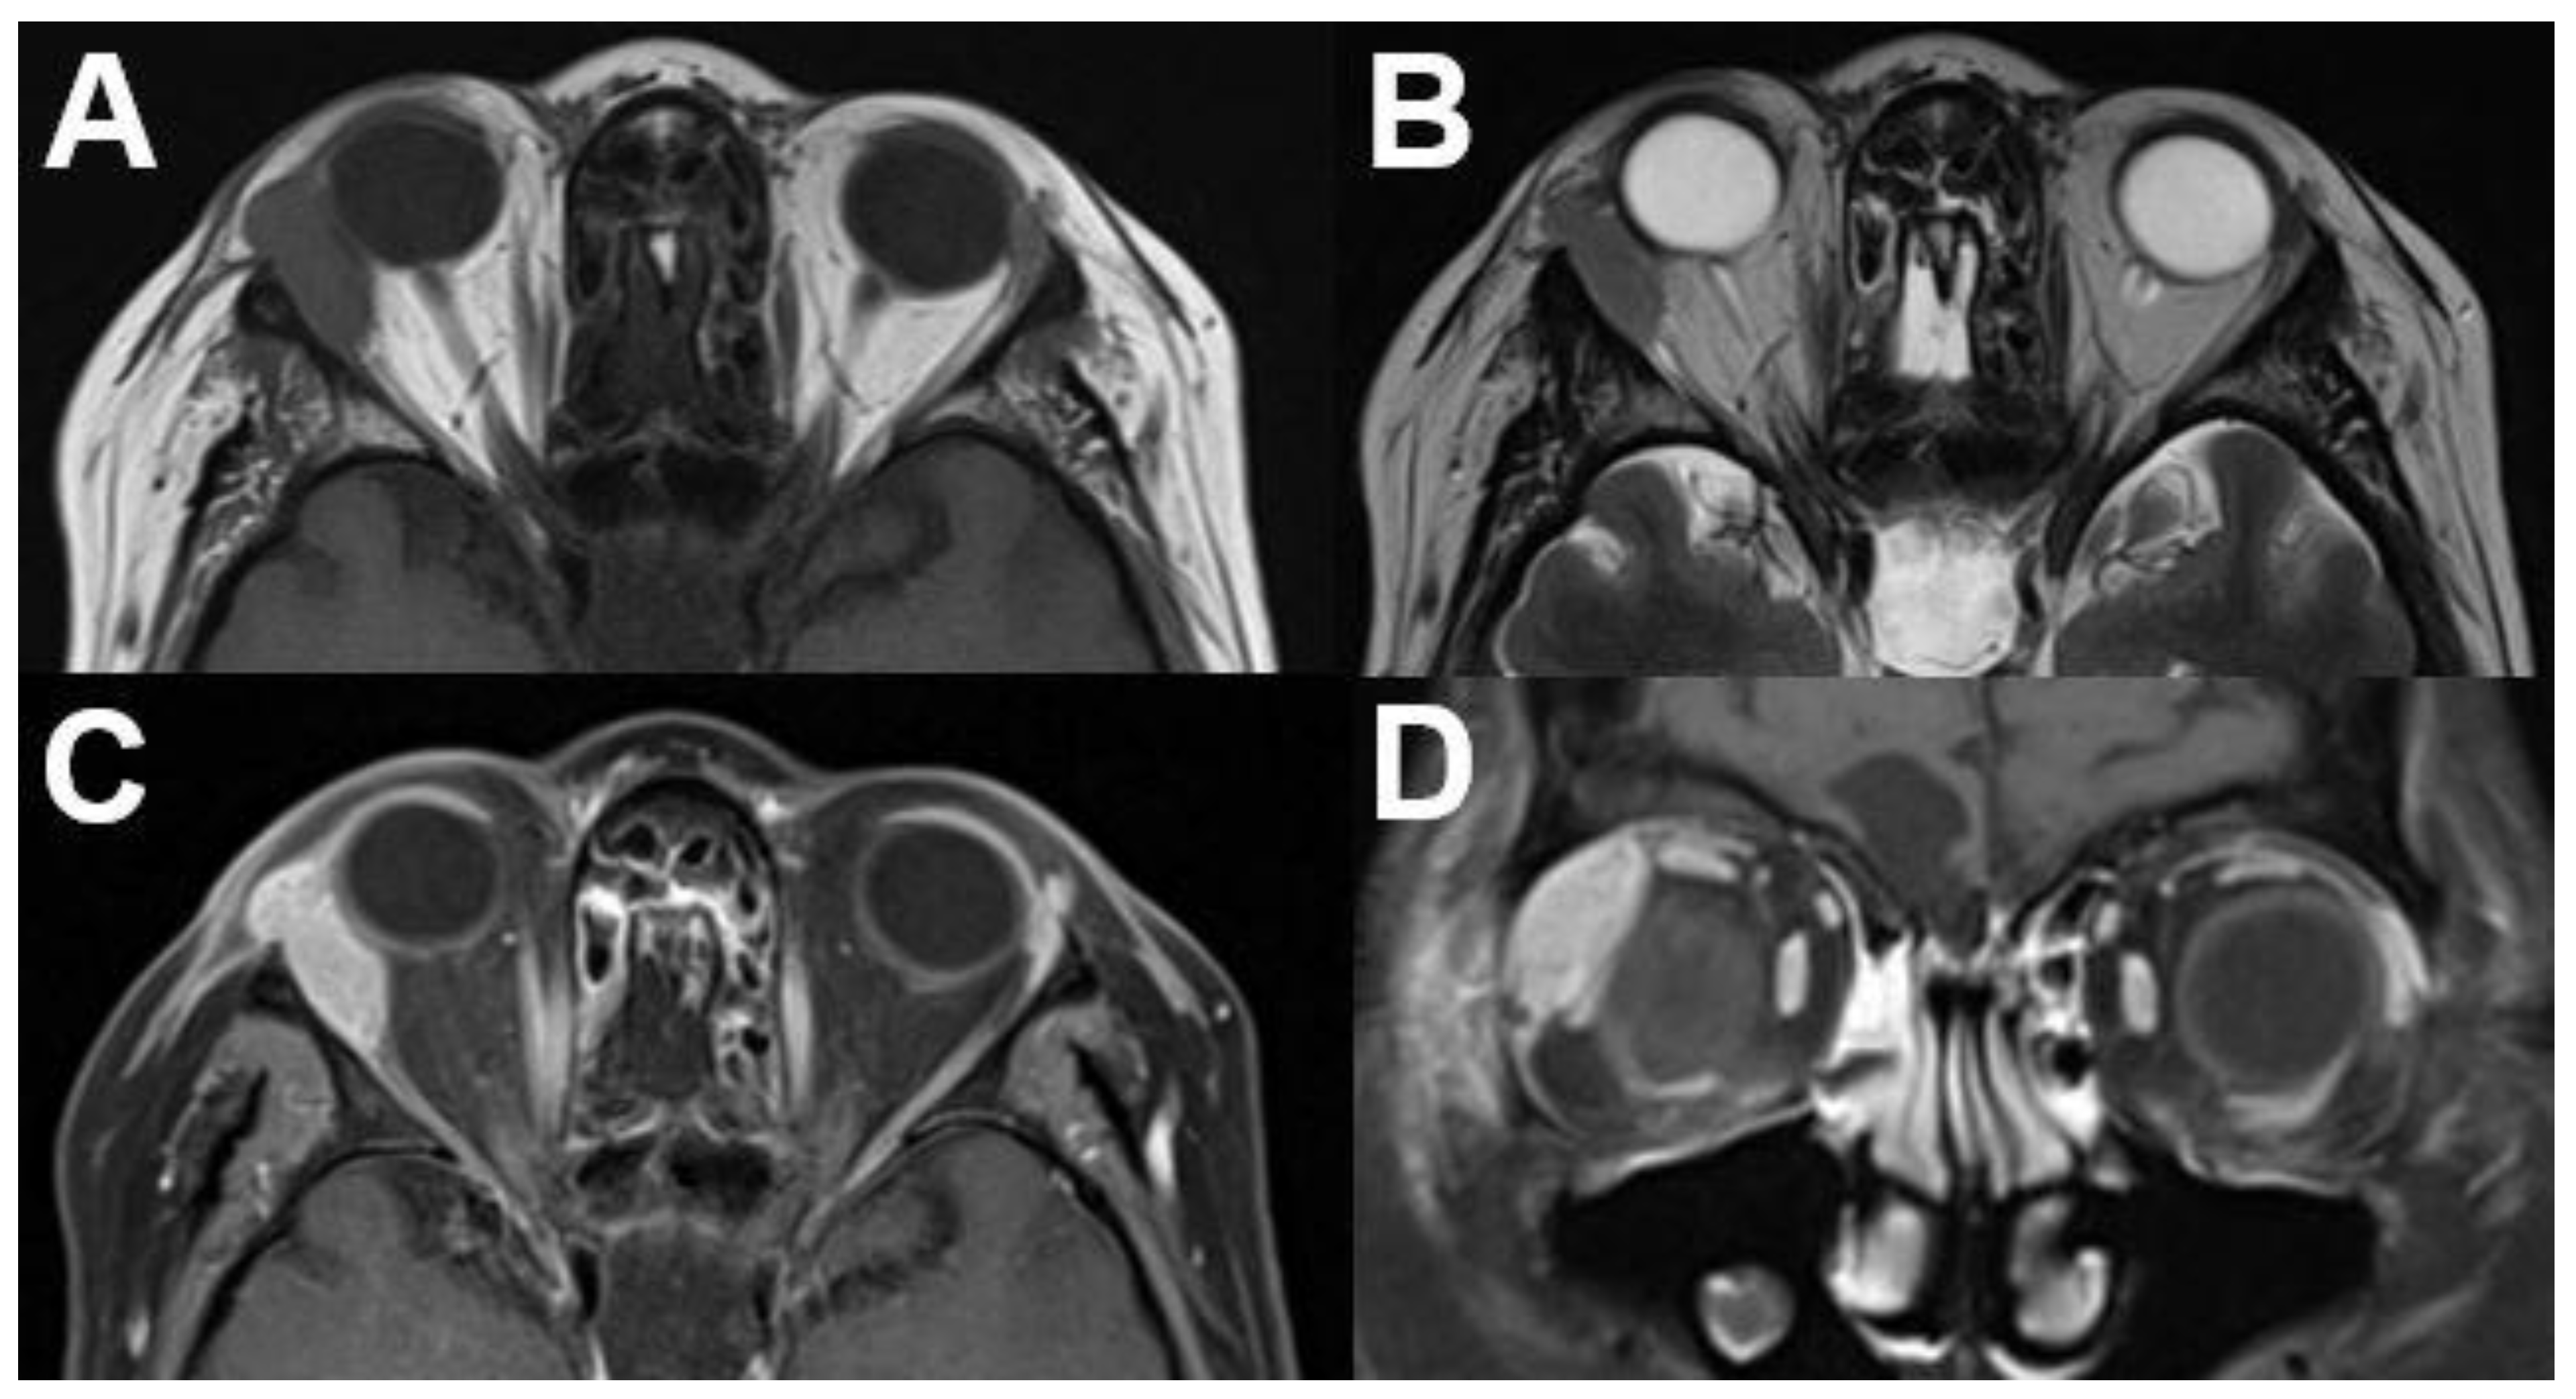

3.1. Intraocular Tumors

3.1.1. Retinoblastoma

3.1.2. Uveal Melanoma